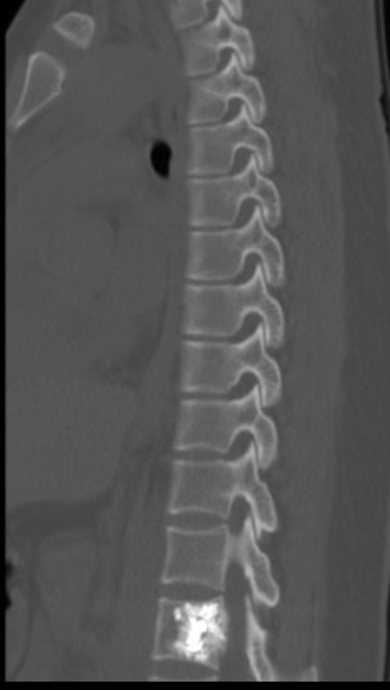

患者一、前列腺癌胸椎脊柱转移行骨水泥注射肿瘤灭活及镇痛术

患者因前列腺脊柱转移导致严重背部疼痛,行骨水泥注射后疼痛完全消失。